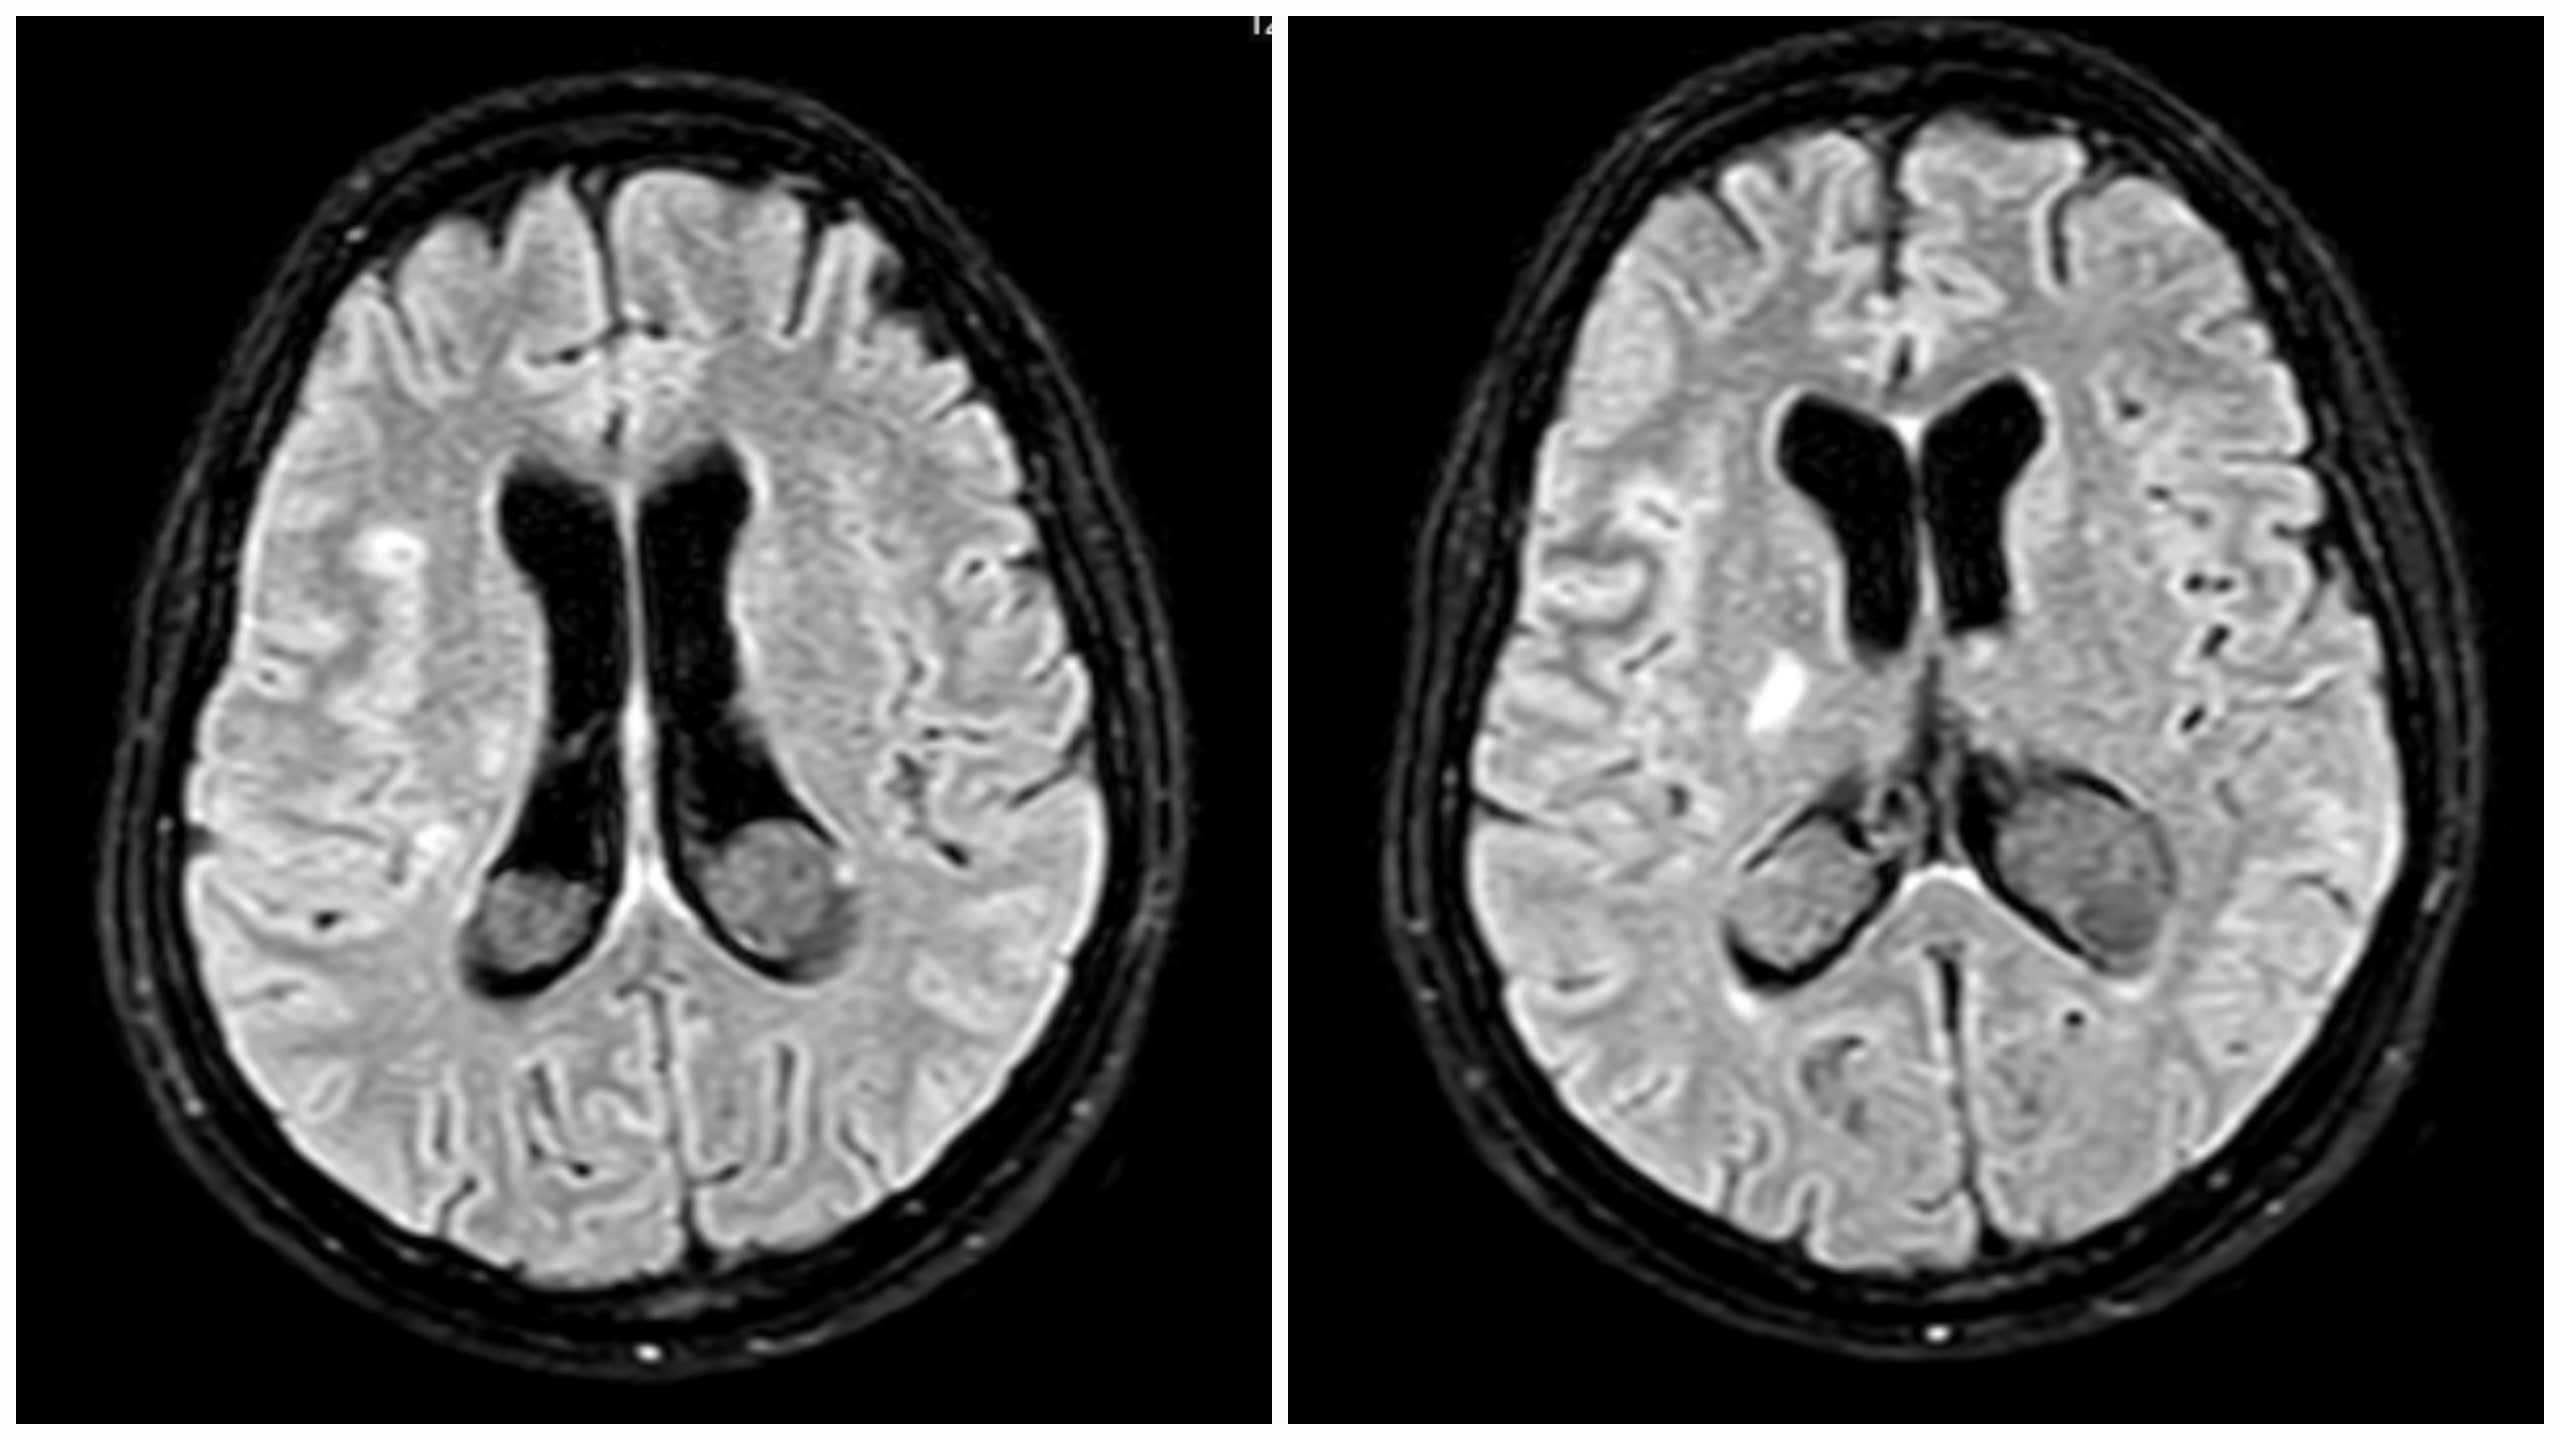

Kết quả MRI sọ cho thấy tổn thương chất trắng rải rác hai bên bán cầu não, giãn não thất, khiến các bác sĩ nghi ngờ một bệnh lý nhiễm trùng thần kinh trung ương. Ngày 7/7, bệnh nhân được chuyển đến Viện Y học nhiệt đới, Bệnh viện Bạch Mai. Kết quả chọc dịch não tủy ghi nhận: tế bào tăng cao, protein cao, glucose hạ thấp. Đây là những đặc điểm điển hình của lao màng não.

Kết quả MRI sọ sản phụ cho thấy tổn thương chất trắng rải rác hai bên bán cầu não